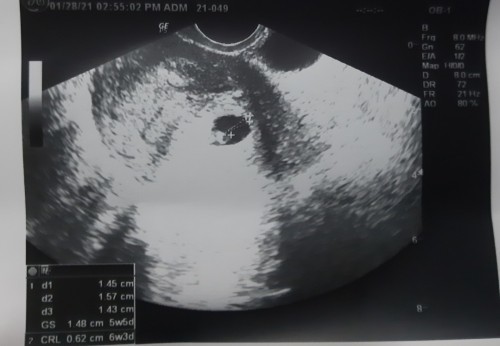

LAST JANUARY 28,2021 IS NAGPA ULTRASOUND PO AKO AND THE RESULT IS 6 WEEKS AND 1 DAY PA BABY KO, SABI NG MAG ULTRASOUND NA DOC.SA AKIN, PERO. NUNG NAG TANONG AMG OB KO WHEN LAST PERIOD KO IS NOV.27,2020 SO SUPPOSEBLY MAG 3 MONTHS NA PO YUNG BABY KO NGAYON. SAAN PO AKO MAG BABASE PO.?? NAGULUHAN NA.PO AKO. #SA NGAYON 8 WEEKS AND 1 DAY NA BABY KO IF.MAG BASE SA ULTRASOUND. #firstbaby #pregnancy #1stimemom